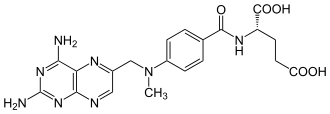

The most widely-used prophylactic drug is methotrexate (MTX), which is normally administered by one of two methods: intravenous injection (IV HD-MTX) and intrathecal injection (IT-MTX).[1][4] Intravenous injection requires a direct injection of high-dose MTX into a patient’s vein;[4] Intrathecal injection, i.e. injection of the drug into the intrathecal space holding cerebrospinal fluid (CSF), is either administered via the Ommaya reservoir, an implanted container passing fluid into the brain, or by lumbar puncture.[1]

The most popular type of CNS prophylactic drug is methotrexate (MTX), an antimetabolite and immunomodulator known to fight lymphoma by interfering with cell growth and division. Contrary to systemic treatments, delivery of MTX to its target site is relatively difficult, due to the drug-expelling properties of the blood-brain barrier via P-glycoprotein trafficking.

One solution is high-dosage methotrexate (IV HD-MTX), defined as ≥5 g/m2, administered by intravenous injection.[7] IV HD-MTX is delivered in addition to standard R-CHOP chemotherapy consisting of rituximab, a monoclonal antibody; cyclophosphamide, doxorubicin and vincristine, chemotherapy drugs; and prednisolone, a corticosteroid. Prophylaxis historically has been given either in between cycles of R-CHOP or upon commencement of R-CHOP. Intercalating treatment was found to increase toxicities during R-CHOP cycles, delaying the delivery of systemic chemoimmunotherapy; on the other hand, given that CNS relapses were reported to be as early as six to eight months from initial diagnosis, prophylaxis is recommended to be given timely.[10]